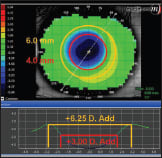

Figure 4. A +3.00D add at 4mm and +6.25D add at 6mm.

Figures 3 and 4 demonstrate a patient with a −5.00D correction. With a 4mm pupil, the amount of add power in the periphery is +3.00D. However, at 6mm the potential add power is again doubled to +6.25D.